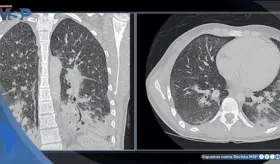

Este caso destaca la importancia de los estudios de imagen multimodales y plantea la necesidad de reconsiderar las estrategias de detección en mujeres no fumadoras, población en la que se observa un incremento creciente de esta neoplasia.